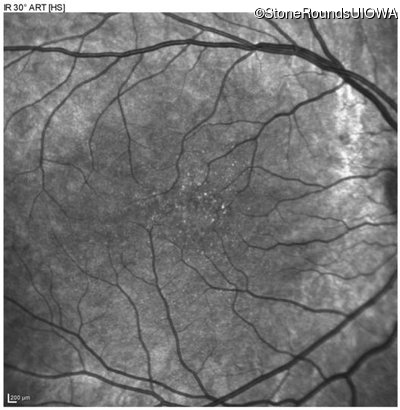

Infrared Fundus Photograph - Right - 20/40 sc

Exemplar